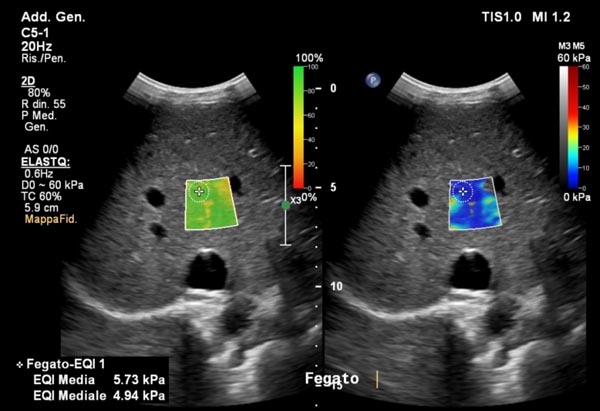

Elastosonografia del fegato: una valida alternativa alla biopsia?

Una delle applicazioni più importanti è la valutazione della fibrosi epatica.Il fegato, in presenza di infiammazioni croniche come le epatiti virali o la steatosi, può sviluppare fibrosi, cioè una sostituzione del tessuto sano con tessuto cicatriziale più rigido.«L’elastosonografia shear wave ci consente di stimare la rigidità del fegato senza ricorrere alla biopsia epatica — spiega il dott. Ivona — offrendo una stima affidabile e ripetibile nel tempo».Questo permette di monitorare l’evoluzione della malattia, valutare l’efficacia delle terapie e individuare precocemente i pazienti a rischio di cirrosi, riducendo l’uso di procedure invasive.

L’esame è indicato per chi soffre di epatite cronica B o C, steatosi epatica, epatopatie alcoliche o patologie autoimmuni del fegato.